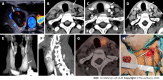

The goal of parathyroid imaging in hyperparathyroidism is not diagnosis, rather it is the localization of the cause of hyperparathyroidism for planning the best therapeutic approach. Hence, the role of imaging to accurately and precisely localize the abnormal parathyroid tissue is more important than ever to facilitate minimally invasive parathyroidectomy over bilateral neck exploration. The common causes include solitary parathyroid adenoma, multiple parathyroid adenomas, parathyroid hyperplasia and parathyroid carcinoma. It is highly imperative for the radiologist to be cautious of the mimics of parathyroid lesions like thyroid nodules and lymph nodes and be able to differentiate them on imaging. The various imaging modalities available include high resolution ultrasound of the neck, nuclear imaging studies, four-dimensional computed tomography (4D CT) and magnetic resonance imaging. Contrast enhanced ultrasound is a novel technique which has been recently added to the armamentarium to differentiate between parathyroid adenomas and its mimics. Through this review article we wish to review the imaging features of parathyroid lesions on various imaging modalities and present an algorithm to guide their radiological differentiation from mimics.